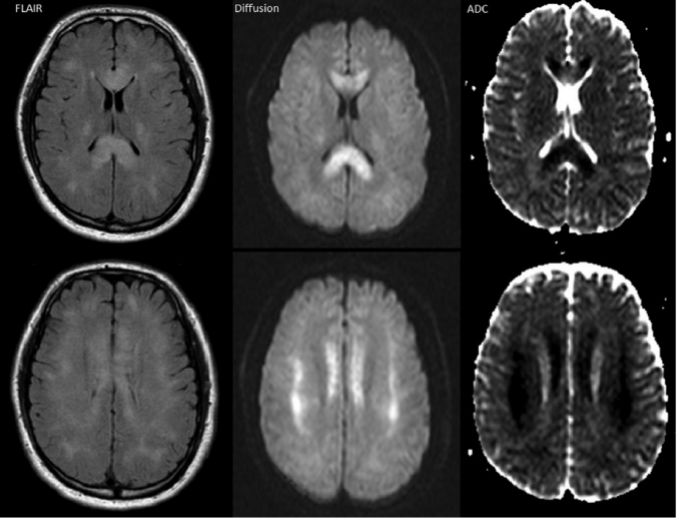

6例患者在首次3T MRI-SWI成像上显示广泛的微出血灶,类似“胡椒粉样”。随访MRI-SWI成像提示微出血灶持续存在,主要分布在整个白质区,包括深束和小脑脚,特别是胼胝体和皮质下白质。第1周内微出血量和程度未增加;在2.5-10年的MRI随访图像上显示,微出血逐渐融合(图3)。另2例患者在随访3T MRI- SWI成像时确定发生微出血,但首次行1.5T MRI-T2序列成像并未发现微出血灶。

图3. 第3天、第8月和第2年的3T MRI-SWI的成像显示,出血瘀斑持续存在并随时间推移微出血灶逐渐融合。